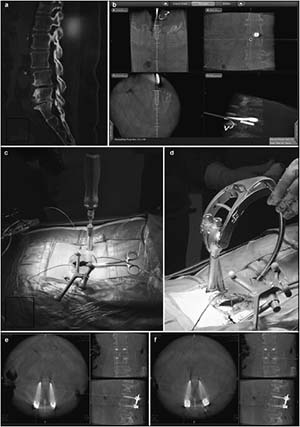

20171023161447 Figure 5 Preoperative, intraoperative, and postoperative images of patients in the percutaneous minimally invasive pedicle internal fixation group. (a) Lumbosacral vertebral computed tomography shows L3 vertebral spondylolisthesis, L3-4 and L4-5 spinal stenosis, intervertebral disc degeneration, and corresponding intervertebral space narrowing. (b) Intraoperative L4 right pedicle screw implantation is performed under navigation. The direction, angle, and depth of screw entry can be seen in real-time, according to the navigation plan. (c, d) Intraoperative screw implantation and bar threading are performed under navigation. (e, f) After screw implantation, O-arm three-dimensional anteroposterior and lateral scans show that the screw is well positioned.